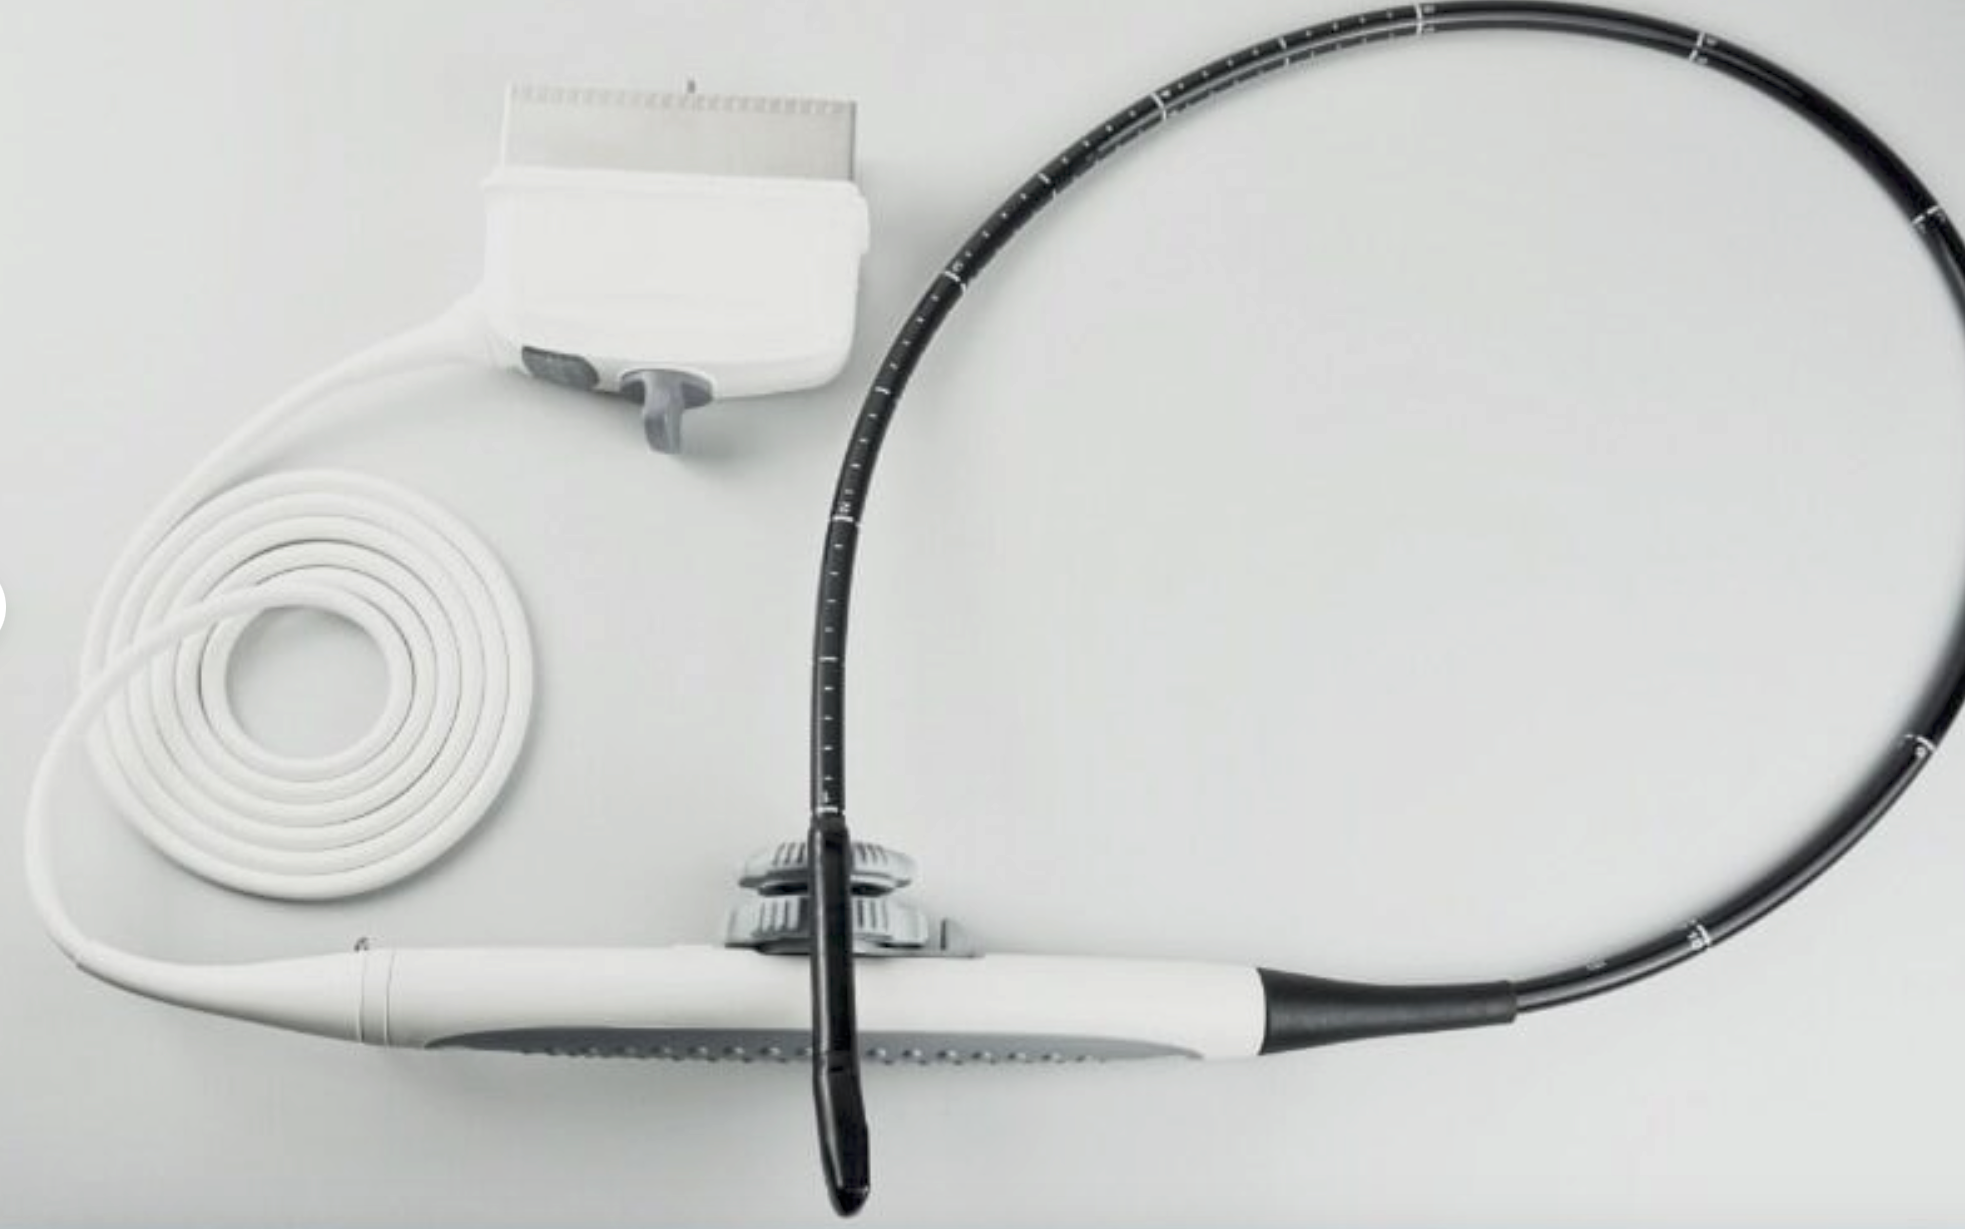

Comes with one rectal probe for large animals, but the probe can be exchanged. Additional probe is $1000.

Linear(L40): L11-4Fc

- Application: Equine and bovine reproduction

- Equine musculoskeletal

- Fish-sexing, egg determination

- Number of element: 80

- Center frequency: 7.5MHz

- Working frequencies: 5 – 10MHz

Linear(L70) L7-4Dc

- Application: Equine and bovine reproduction

- Equine musculoskeletal

- Fish-sexing, egg determination

- Number of element: 80

- Center frequency: 5.0MHz

- Working frequencies: 3 – 7MHz